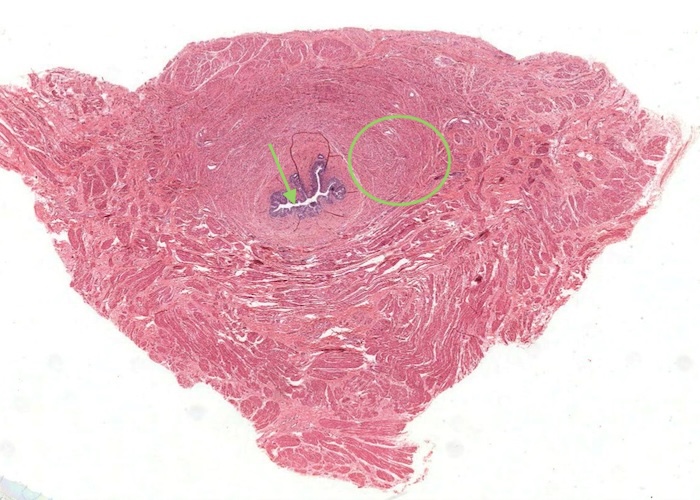

The layers of the bladder are basically the same as in the ureter. However, the muscle layer is much thicker and includes a third sheet of smooth muscle with oblique orientation. Of course for a spherical organ like the bladder "longitudinal", "circular", and "oblique" are somewhat formalistic terms. In any case, sheets of smooth muscle running in different orientations are discernable although somewhat indistinct. The smooth muscle became “super contracted” when put in fixative. This has thrown the mucosa into pronounced folds. The epithelium also is over contracted in places. When you view this histological section find some nice views of rounded up umbrella cells with their acidophilic apical borders. Look further and you will come across patches of transitional epithelium in a relaxed state.

All the excretory passages (apart from the urethra) have a mucosa with transitional epithelium and muscularis and an outer adventitia.

Transitional epithelium is impermeable to water and salts and can accomodate the distension of the bladder as it fills with urine. In this image of "relaxed bladder" there are about 8 cell layers but make sure you notice how these layers "flatten out" in the "stretched bladder" image in the later item. Notice how the surface cells are cuboidal and bulge into the lumen of the bladder but their apex is curved or shaped like a dome so they are often referred to as "umbrella cells". The connective tissue below the epithelium is very cellular.

When the lumenal epithelium of the bladder is distended (stretched) the cell layers are reduced as the cells flatten and unfold as the lumenal surface area increases. The surface cells that were once a cuboidal cell undergo a "transition" to become a squamous cell. Compared to the relaxed bladder this epithelium has a less "scalloped" appearance as the "plaques" position themselves on the apical cell surface.